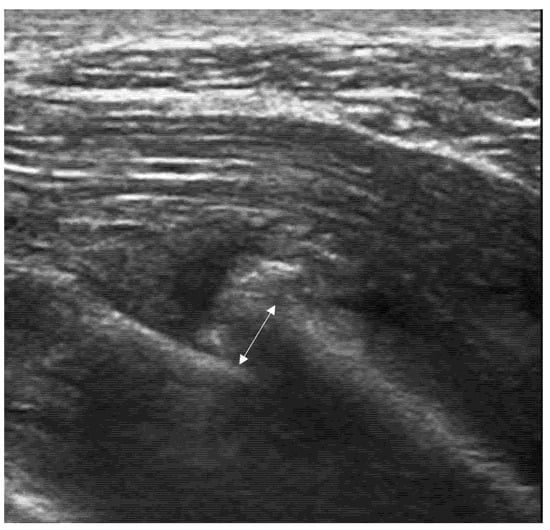

4.2. Sonoanatomy of Fractures [Figure 5, Figure 6, Figure 7 and Figure 8]

- Irregularity, interruption, or gaps in the cortical line: the cortical bone normally appears as a continuous, bright echogenic line, which is interrupted or irregular in the presence of a fracture.

- Reverberation artifacts within or adjacent to the fracture gap (also known as the “chimney sign”): these repetitive echoes are caused by ultrasound waves reflecting off the fracture surfaces.

- Local hematoma or soft tissue edema: fluid collections or increased echogenicity near the fracture site indicating bleeding and inflammation.

- Periosteal thickening or elevation: the periosteum may appear thickened or lifted due to injury or early callus formation.

- Joint effusion and liphemarthrosis: fluid accumulation within a joint, sometimes containing fat droplets, which often indicates an intra-articular fracture.